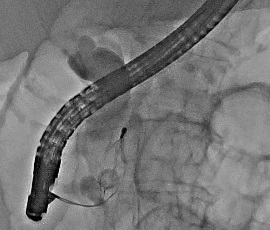

[総胆管結石] 手術:内視鏡的乳頭括約筋切開術:EST

]腺画像